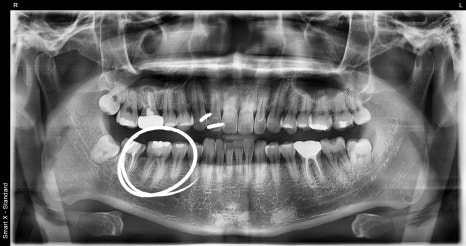

Panoramic and intraoral photos taken at the first visit

Through panoramic X-ray imaging,

we confirmed that a deep cavity had progressed in the first molar on the lower right (first molar).

Fortunately, it had not reached the nerve, so the tooth could be saved with inlay treatment

without root canal treatment.